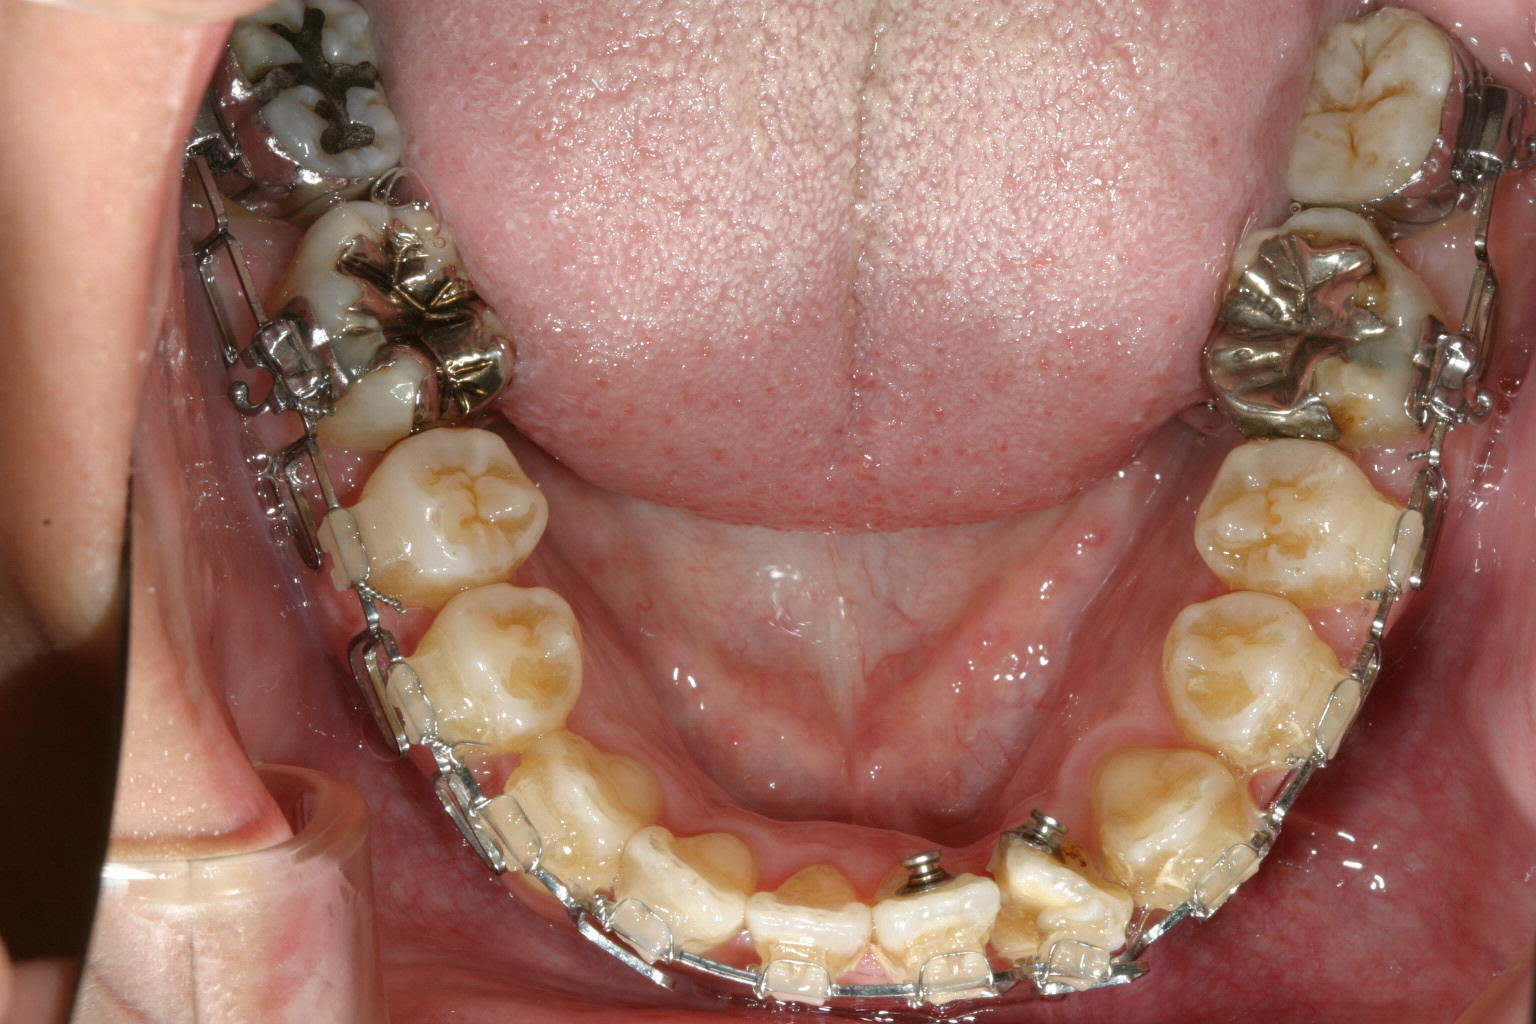

下顎の両側切歯が90度回転しています。 これが難儀なんです。 ワイヤーを留める為のブラケットを何度か貼りなおす必要が有ります。

下顎はこの90度回転した歯に悪戦苦闘しています。笑

1年9カ月後です。 前回の写真よりもアーチがU字になってきているのが分かります。

下顎の綺麗なU字になりました。